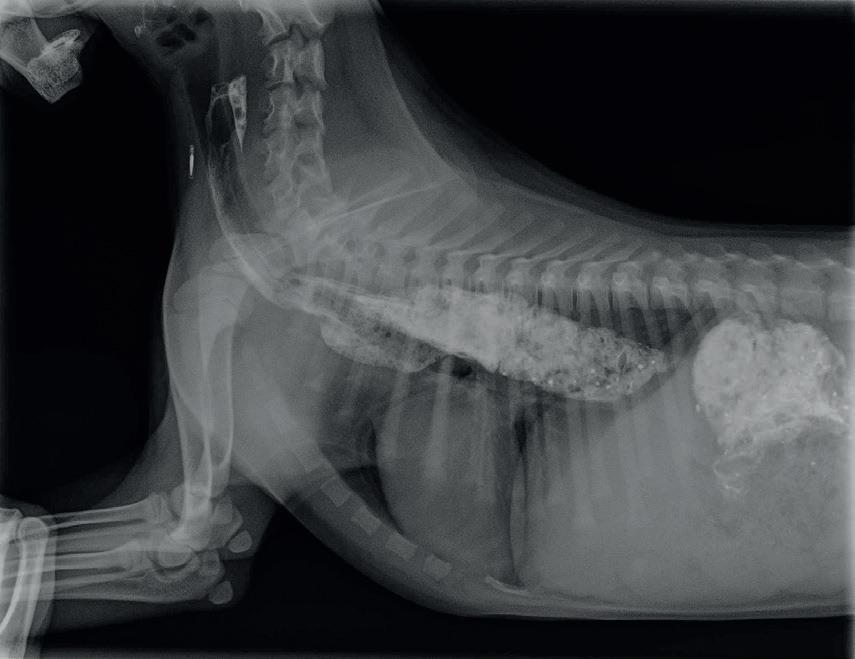

En la radiografía de contraste (fig. 3) aún se evidencia la dilatación esofágica con un DER de 0,68, por lo que viendo que la perra se encuentra mejor sintomáticamente y no presenta efectos secundarios achacables a la medicación se decide prolongar el tratamiento. Según la descripción de un caso clínico publicado (5),con la prolongación del tratamiento más allá de 15 días el animal siguió mejorando. Se mantuvo la alimentación en posición erguida, durante

propietarios son reticentes a retirar la medicación por lo que se reduce la dosis a la mitad. A los dos semanas del cambio la perra no ha tenido ningún episodio de regurgitación por lo que se retira la medicación y se le repite la radiografía de contraste observándose una disminución significativa del DER ( Fig.4),aún se le mantiene la alimentación en posición erguida.

Desde entonces lleva 10 meses desde que dejó la medicación y 9 desde come en posición normal y no ha presentado más episodios de disfagia o regurgitación, su condición corporal es de 5/9, se le ha realizado la ovariohisterectomía sin complicaciones y en las radiografías de control (figs. 5 y 6) no se aprecia ya dilatación esofágica y presenta un vaciado esofágico rápido y completo.